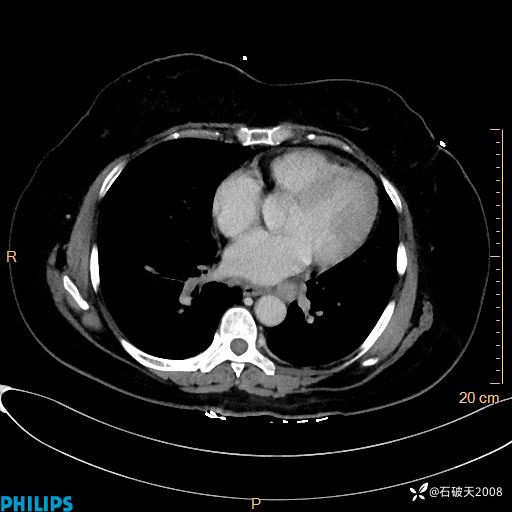

静脉期